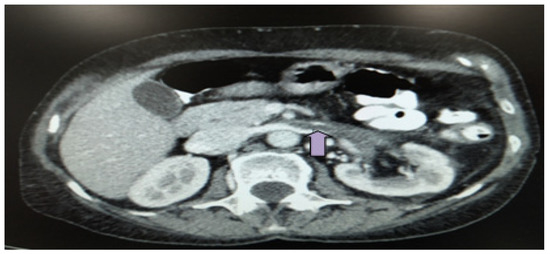

2. Case Description